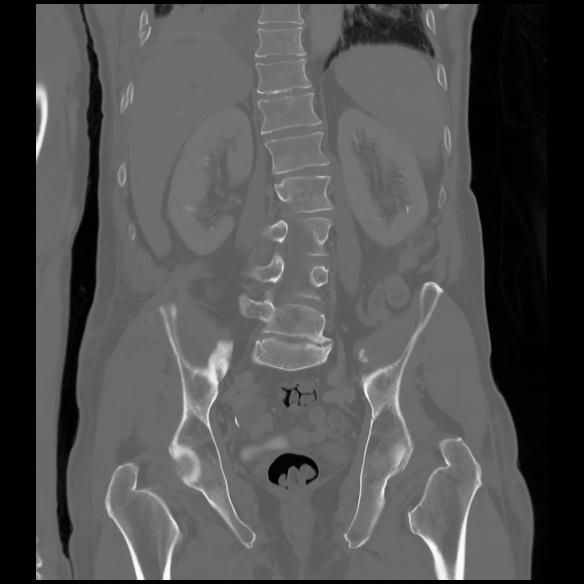

6 CUERPO,CE,Coronal,3.000,CUERPO,Coronal,